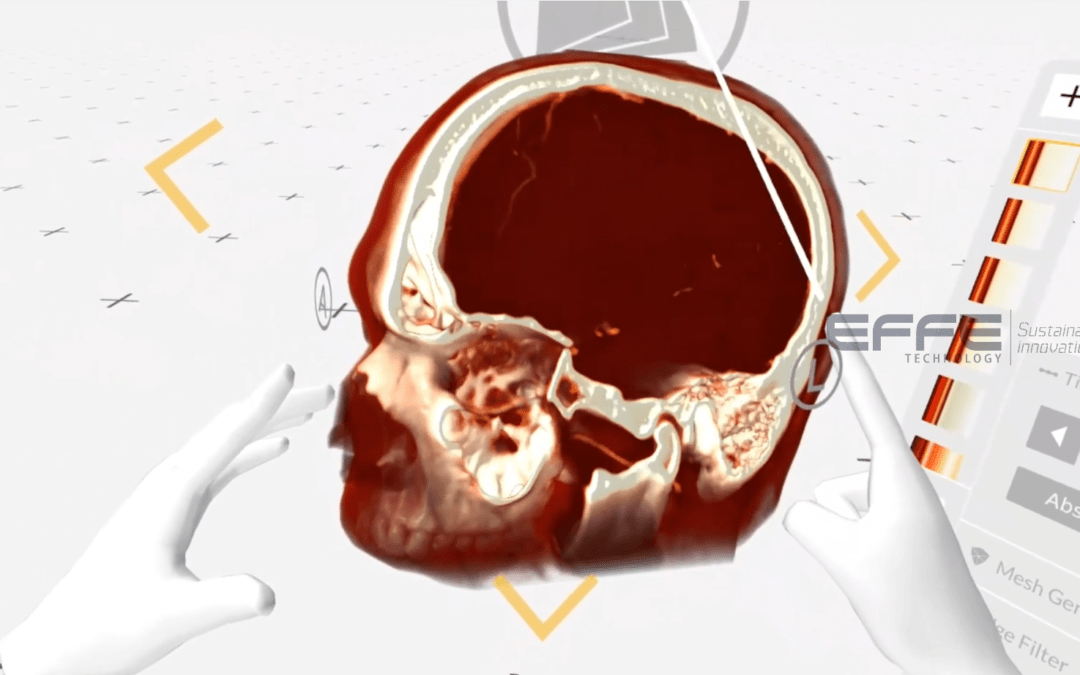

Overview Understanding Brainstem Neuroanatomy is one of the most challenging aspects of medical education. The...

Overview Understanding the human brain—especially the brainstem and intricate neural pathways—requires more than...